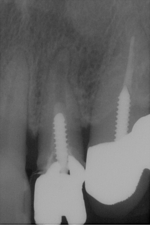

術前 ➡

術中

根の先に影(感染)が出てしまい根の治療を行わないといけないのですが以前他院にて処置を施した古い薬が入っています

画像を見ると手前の根にはしっかりと先まで薬が入っていません(1枚目の画像)